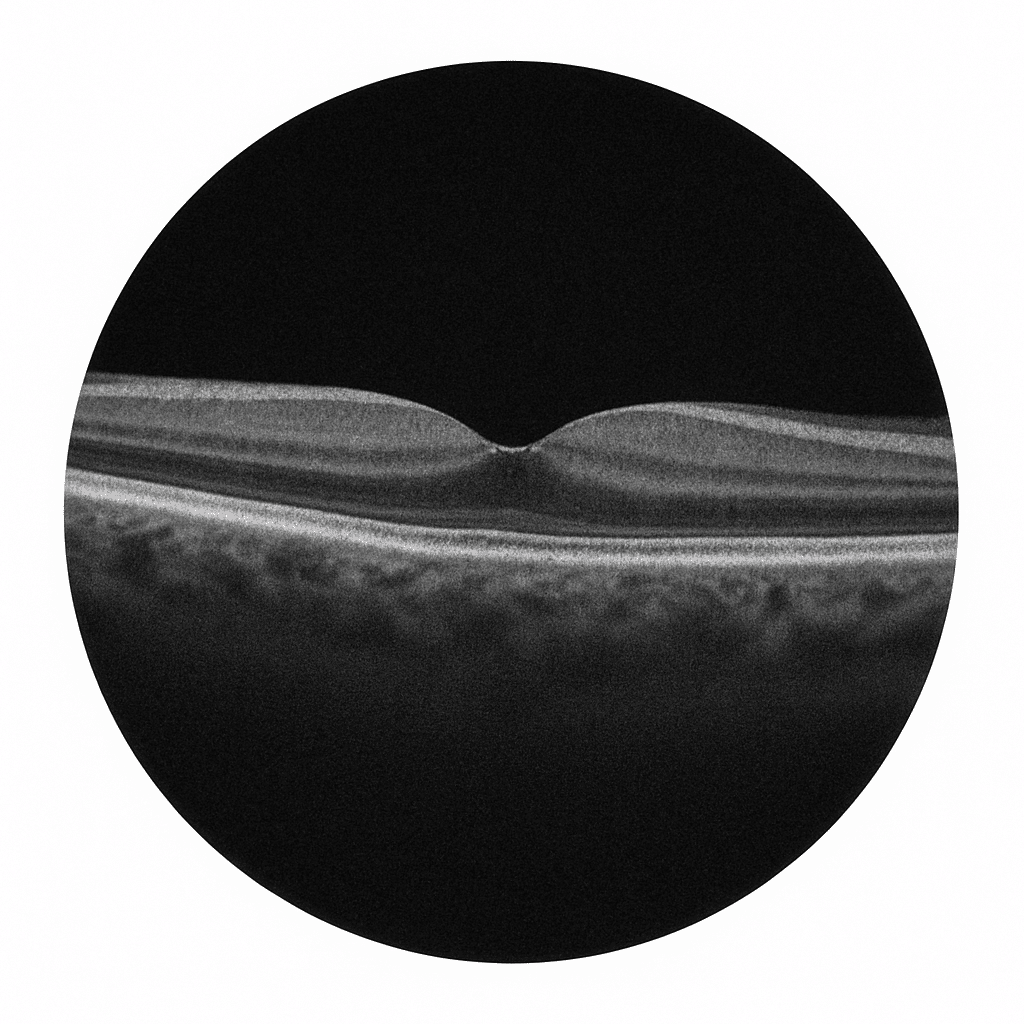

OCT (Tomographie en Cohérence Optique)

L’OCT (tomographie par cohérence optique) est un examen d’imagerie de la rétine devenu incontournable en ophtalmologie. Il permet d’analyser avec une grande précision la macula – la zone centrale de la rétine responsable de la vision fine.